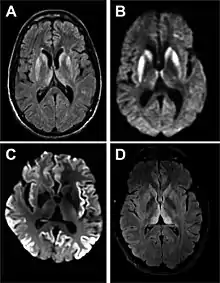

MRI of iCJD because of growth hormone

The defective protein can be transmitted by contaminated harvested human brain products, corneal grafts,[23] dural grafts,[24] or electrode[25] implants and human growth hormone.[26]

• MRI of the brain – often shows high signal intensity in the caudate nucleus and putamen bilaterally on T2-weighted images.

Imaging of the brain may be performed during medical evaluation, both to rule out other causes and to obtain supportive evidence for diagnosis. Imaging findings are variable in their appearance, and also variable in sensitivity and specificity.[43] While imaging plays a lesser role in diagnosis of CJD,[44] characteristic findings on brain MRI in some cases may precede onset of clinical manifestations.[45]

Brain MRI is the most useful imaging modality for changes related to CJD. Of the MRI sequences, diffuse-weighted imaging sequences are most sensitive.[46] Characteristic findings are as follows:

• Focal or diffuse diffusion-restriction involving the cerebral cortex and/or basal ganglia. In about 24% of cases DWI shows only cortical hyperintensity; in 68%, cortical and subcortical abnormalities; and in 5%, only subcortical anomalies.[47] The most iconic and striking cortical abnormality has been called "cortical ribboning" or "cortical ribbon sign" due to hyperintensities resembling ribbons appearing in the cortex on MRI.[48] The involvement of the thalamus can be found in sCJD, is even stronger and constant in vCJD.[49]

• Varying degree of symmetric T2 hyperintense signal changes in the basal ganglia (i.e., caudate and putamen), and to a lesser extent globus pallidus and occipital cortex.[44]